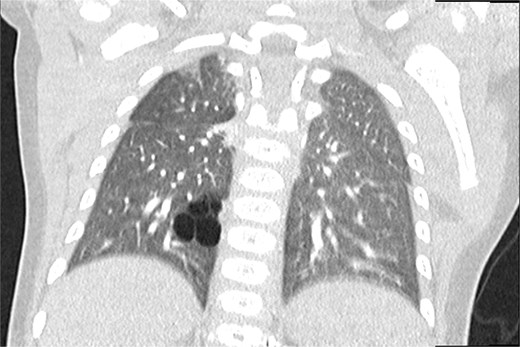

All neonates were clinically asymptomatic after birth. There were no episodes of respiratory distress, desaturation, or feeding difficulties. Cardiopulmonary examinations were normal in all patients. Routine postnatal chest radiography was unremarkable in all four infants, with no visible cystic lesions or lung asymmetry. These findings confirmed the limited diagnostic value of conventional radiography in asymptomatic CPAM. Definitive postnatal imaging was performed using contrast-enhanced chest CT at a mean age of 13 months (range 11–15 months). CT imaging provided clear visualization of the cystic malformations, precise lobe localization, and detailed vascular anatomy (Fig. 1). All CT-scans were performed under conscious sedation using oral midazolam. Postnatal MRI was deliberately avoided to prevent the need for general anesthesia in infancy, as its additional diagnostic benefit over CT was considered limited for surgical planning.

Chest CT (coronal plane) showing a CPAM in the lower lobe of the right lung.